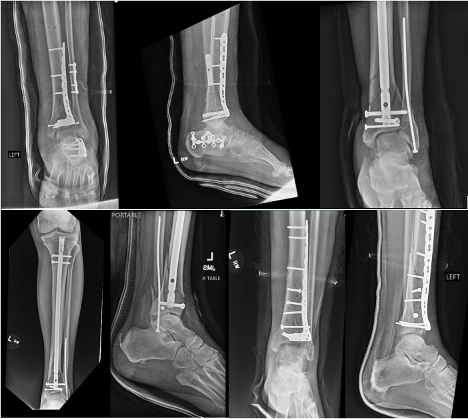

Staged ORIF following external fixation has been the standard protocol in treatment of pilon fractures. Surgeons may pursue definitive surgical management once skin wrinkles appear and fracture blisters resolve. Authors have described multiple incisional approaches, varying depending on the fracture pattern, overall goals of fixation, and location of soft tissue compromise. Although some literature shows no difference in complication rates for early ORIF, more substantial literature shows a decrease in soft tissue complications and better functional outcomes with a two-stage approach.13,23,24 Consider transsyndesmotic fixation in low-energy rotational injuries.25 Authors have described minimally invasive techniques, most often used along the medial column, which theoretically decrease wound healing complications. Lau and colleagues found a high surgical site infection rate after medial subcutaneously placed plates in distal tibia fractures, though they ultimately found no significant difference on overall outcome.26 The challenges of nonunion and angular rotation are present with minimally invasive techniques, necessitating further comparative studies for a more thorough evaluation of its utilization (Figures 3 and 4).